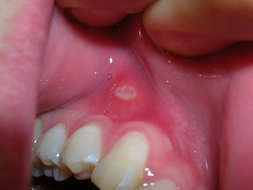

Aft yarası, ağız içinde meydana gelen küçük, yuvarlak, ağrılı lezyonlardır. Genellikle beyaz veya sarı bir zemin üzerinde kırmızı bir halka ile çevrilidir. Aft yaraları, bireylerin yaşam kalitesini olumsuz etkileyebilir ve çeşitli nedenlerle ortaya çıkabilir. Bu makalede, aft yaralarının belirtileri, nedenleri ve tedavi yöntemleri detaylı bir şekilde ele alınacaktır. Aft Yarasının BelirtileriAft yaralarının belirtileri genellikle aşağıdaki gibi sıralanabilir: